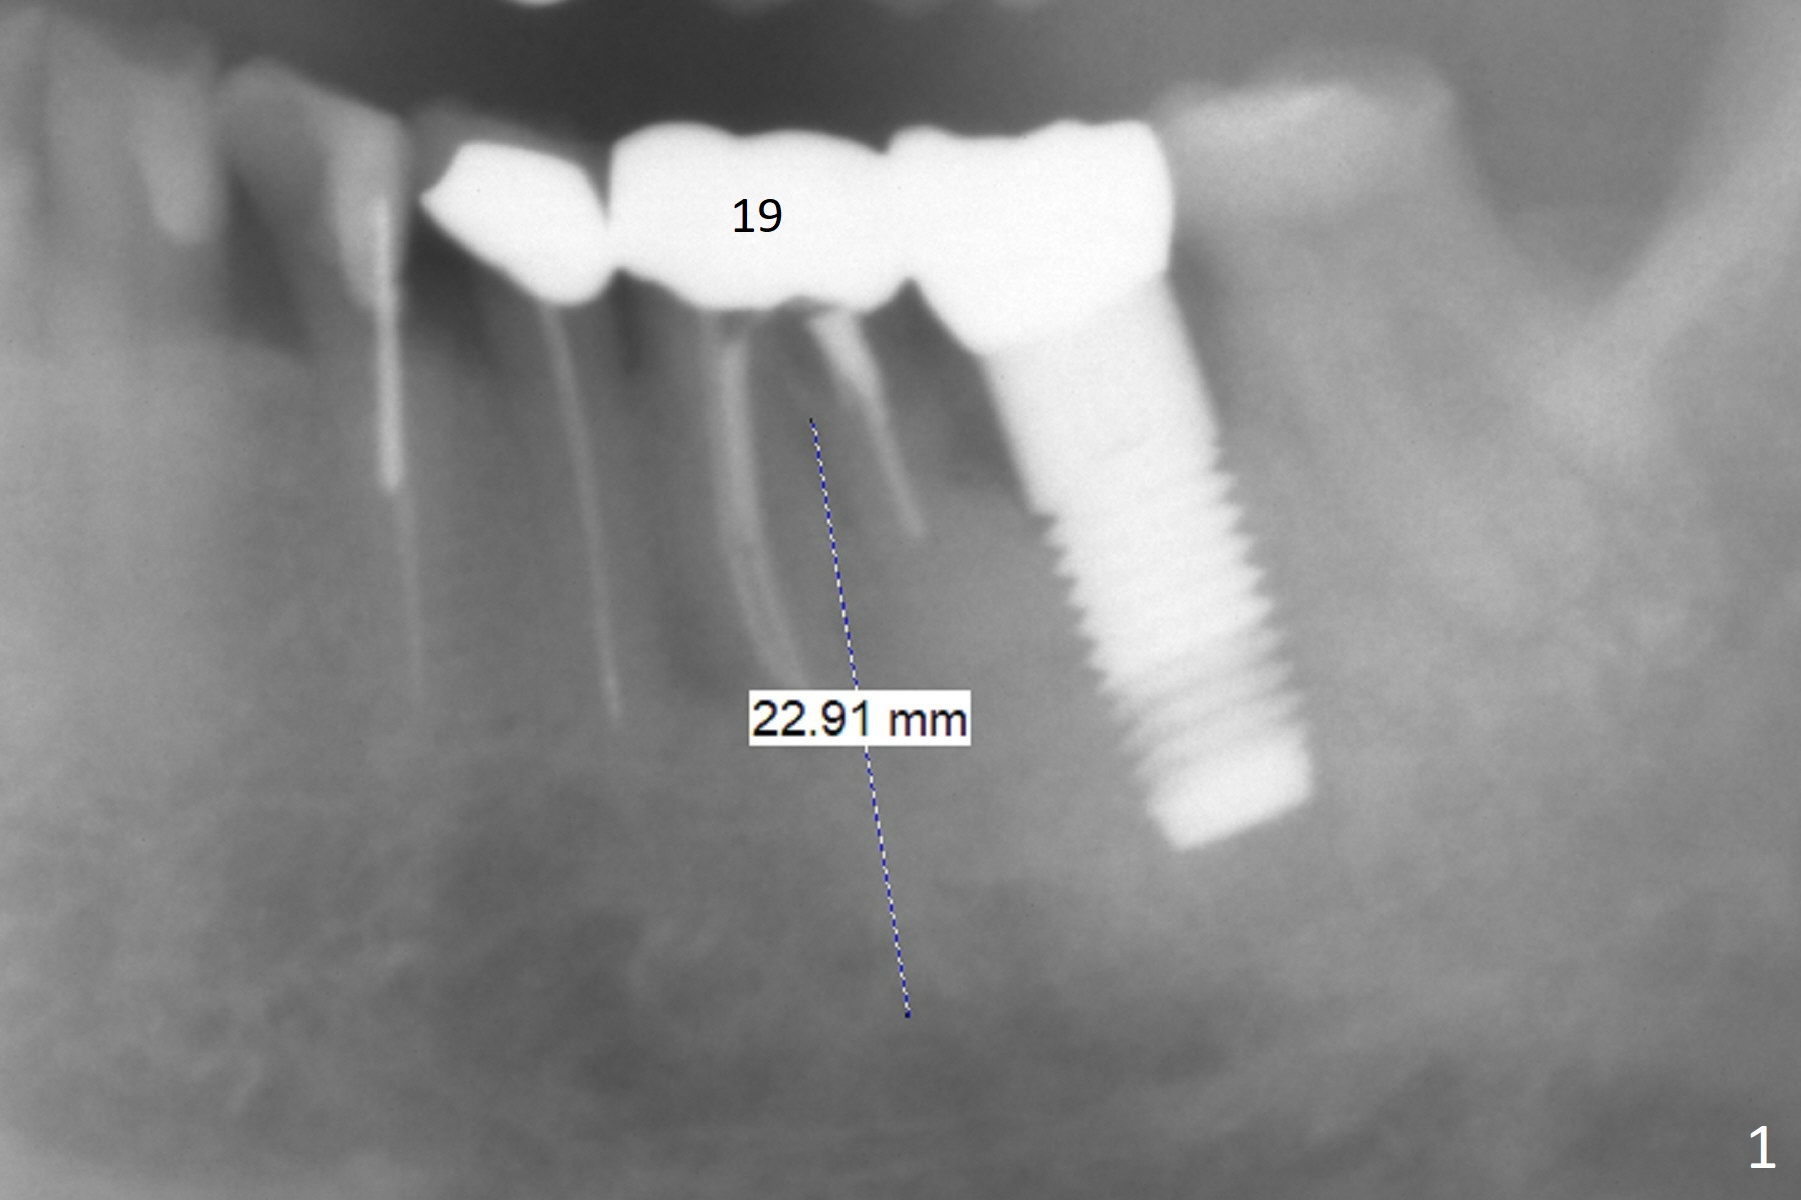

A 87-year-old man loses #19 crown and post recently (Fig.1). A new implant system will be tried. It has 2 main features. There are 2 sets of drills (short and long). Every time try short ones unless the neighboring teeth are extremely long. There are several lengths of stoppers (as short as 5.7 mm) so that we do not have to use short stoppers from DIO Sinus Master Kit. If a sample implant (5x10 mm, Fig.2) does not achieve primary stability, shift to UF, but still use IS drill for 13 mm (Fig.3). Take preop PA. Prepare surgical handpiece for sectioning. Place bone graft to the defect between #18 and 19.